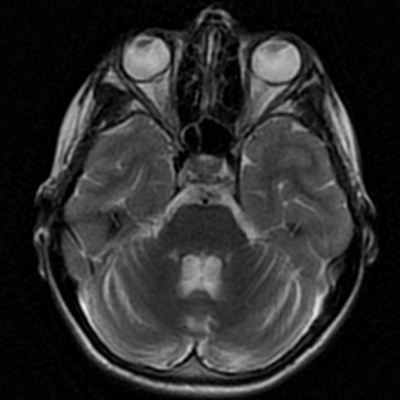

- B) Aksiyel T1A görüntülerde her iki lentiform ve kaudat nukleuslarda, talamuslarda simetrik hiperintensite (oklar) izleniyor. Bu düzeyde tariflenen sinyallerin SWI ve faz görüntülerde kalsifikasyon ile uyumlu olduğu görülmektedir (oklar). T2A görüntüde yaş ile uyumsuz serebellar atrofi ile uyumlu foliada derinleşme ve 4. ventrikül genişliğinde artış izlenmektedir (oklar).

- BT’de birden fazla lokalizasyonda multipl enfarkt benzeri odaklar ve özellikle ileri yaş hastalarda belirginleşen bazal gangliyon kalsifikasyonları izlenebilir. Lezyonlar çoğunlukla pariyeto-oksipital ve pariyeto-temporal bölgelerde yoğunlaşır ve serebral atrofi eşlik edebilir.

- MRG’de akut fazda T2/FLAIR hiperintensiteyle birlikte giral şişme ile karakterize enfarkt-benzeri lezyonlar ve subkortikal beyaz cevher tutulumu görülür. DWI’da artmış sinyal dikkat çekmekle birlikte ADC değerlerinin normal ya da hafif artmış olması, baskın sürecin vazojenik ödem olduğunu gösterir.